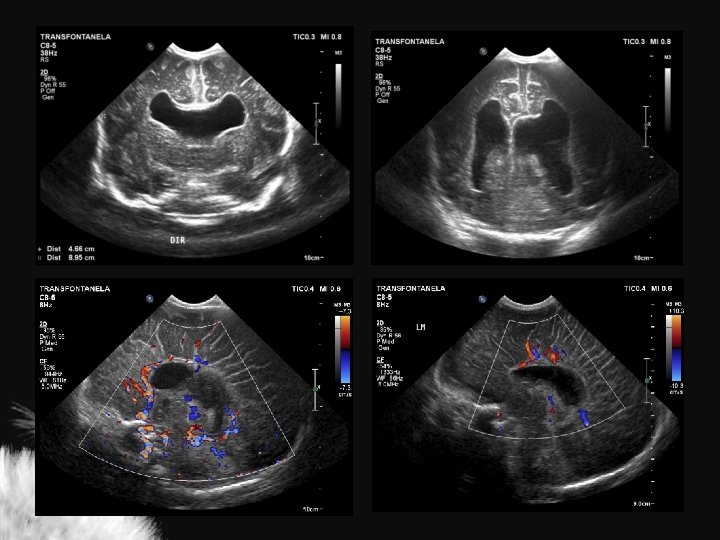

MACROCRANIA

Macrocrania • Macrocrania benigna hidrocefalia benigna da infância, coleção extra axial benigna da infância • Condições patológicas: • US – Coleções anecóicas – Formato em V – Sulcos e giros proeminentes – Ventrículos normais ou proeminentes – Pia-aracnoide com ecogenicidade normal – Higroma subdural – Hematoma subdural – Abscesso secundário a meningite – Coleções ecogênicas – Formato em U – Sulcos e giros deslocados ou achatados – Ventrículos alargados – Pia-aracnoide hiperecogênica

Mc Cluney et al. AJNR 13: 1335 -1339 Chen et al. Radiology 201: 389 -392

Hidrocefalia benigna da infância – sinal da veia cortical positivo

Coleção subdural – sinal da veia cortical negativo